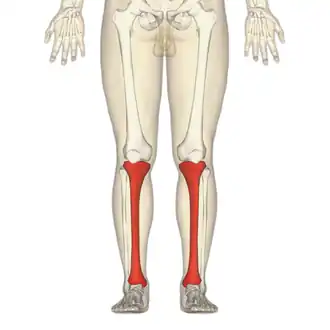

The photographs and radiographs illustrate the application and emplacement of an external fixator, an Ilizarov apparatus, to repair the open fracture of the lower left leg of a man. The photographs were taken four weeks after the patient fractured the shinbone (tibia) and the calfbone (fibula) of his left leg, and two weeks after the surgical emplacement of the Ilizarov apparatus to immobilise the leg and isolate the wound and fracture site to facilitate healing.